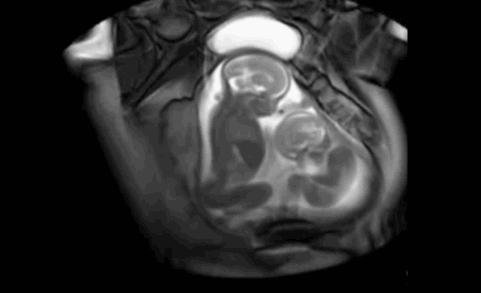

小baby不依不饶,继续战斗

大baby好像开始说话了

猜猜他在说什么呢